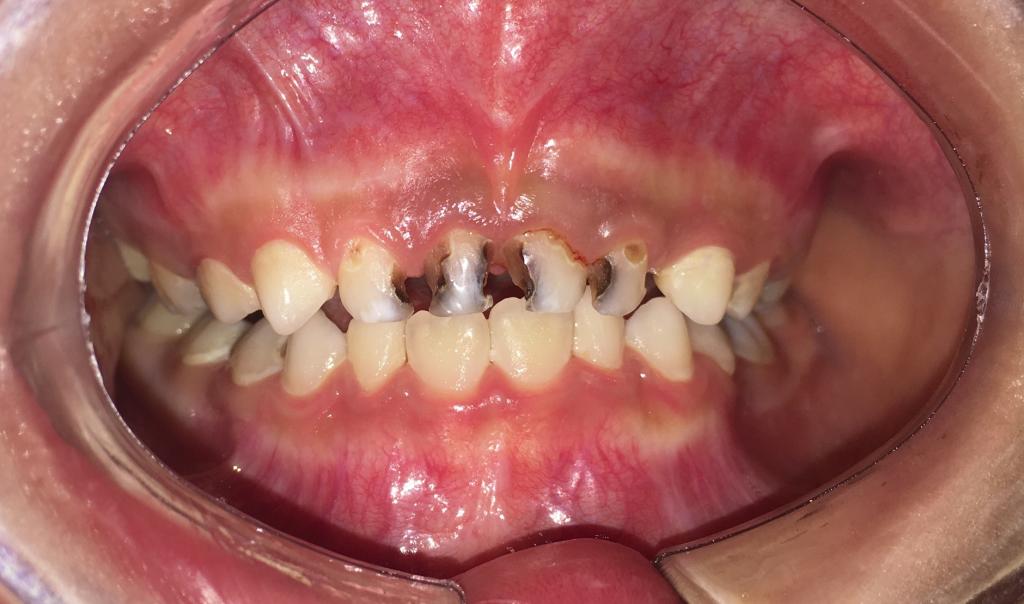

龋齿

吃糖的最大坏处就是容易导致蛀牙,糖摄入过多,加上不注意口腔卫生致使食物残渣残留,糖会被细菌分解发酵,产生酸性物质,侵蚀牙齿,使牙齿遭到破坏。预防宝宝蛀牙,糖是头号大敌。